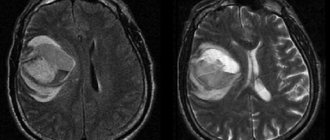

При проявлении хотя бы одного из вышеперечисленных симптомов, человеку необходимо обратиться к врачу для обследования головного мозга. Работа коры проверяется при помощи методики SPECT, которая основана на сравнении активности данной зоны мозга в состоянии покой и стимуляции. При патологиях в стимулированном режиме активность либо будет оставаться на месте, либо пойдёт на спад.

Одними из основных причин появления патологий в являются кровоизлияние в мозг, вследствие получения травмы головы или обширного инсульта и интоксикация организма вредными веществами (алкоголь, яды, токсины и др.). Также нередки случаи отклонения ПК из-за генетических и вирусных заболеваний, которые поражают центральную нервную систему (ЦНС). Кроме того на выполнение функций ПК могут влиять продолжительный стресс и недостаток сна.